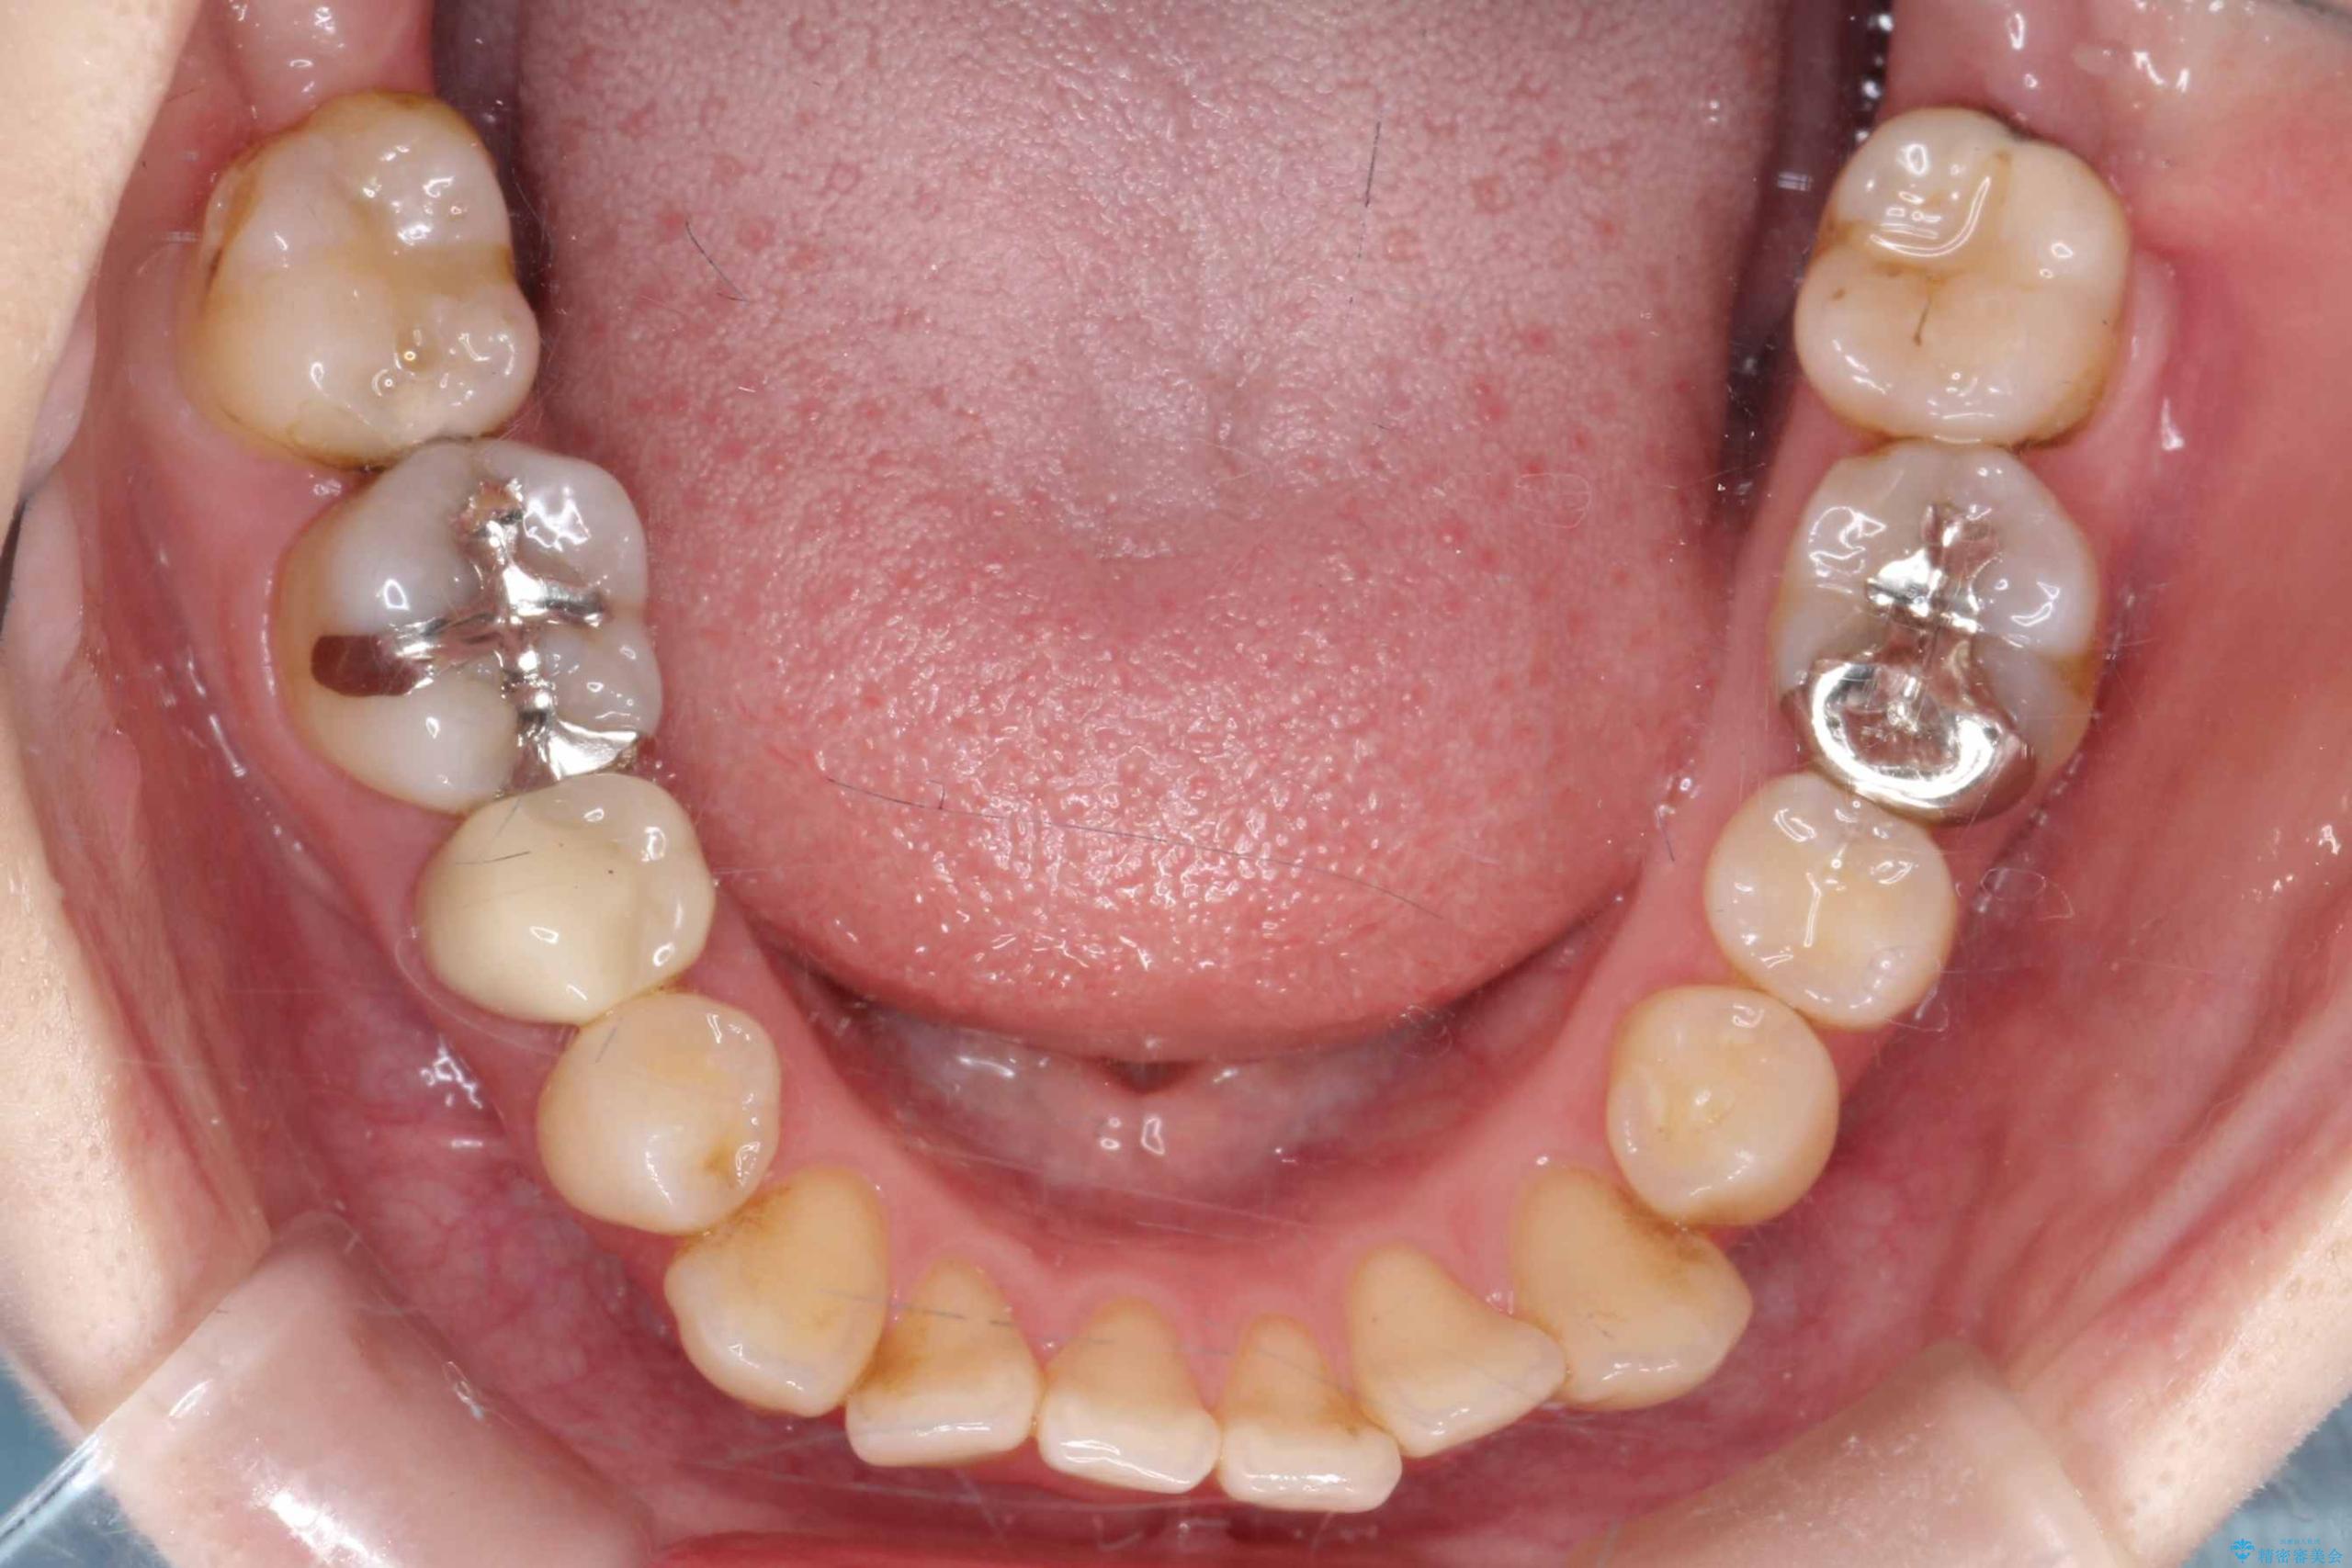

- 開咬と歯のデコボコ(叢生)、八重歯を主訴にご来院された患者様です。

矯正の精密検査の結果、上顎左右4番および下顎左右5番の計4本を抜歯し、ワイヤー矯正(クリア装置)にて治療を行いました。

虫歯があったので、虫歯治療は矯正前に行っています。